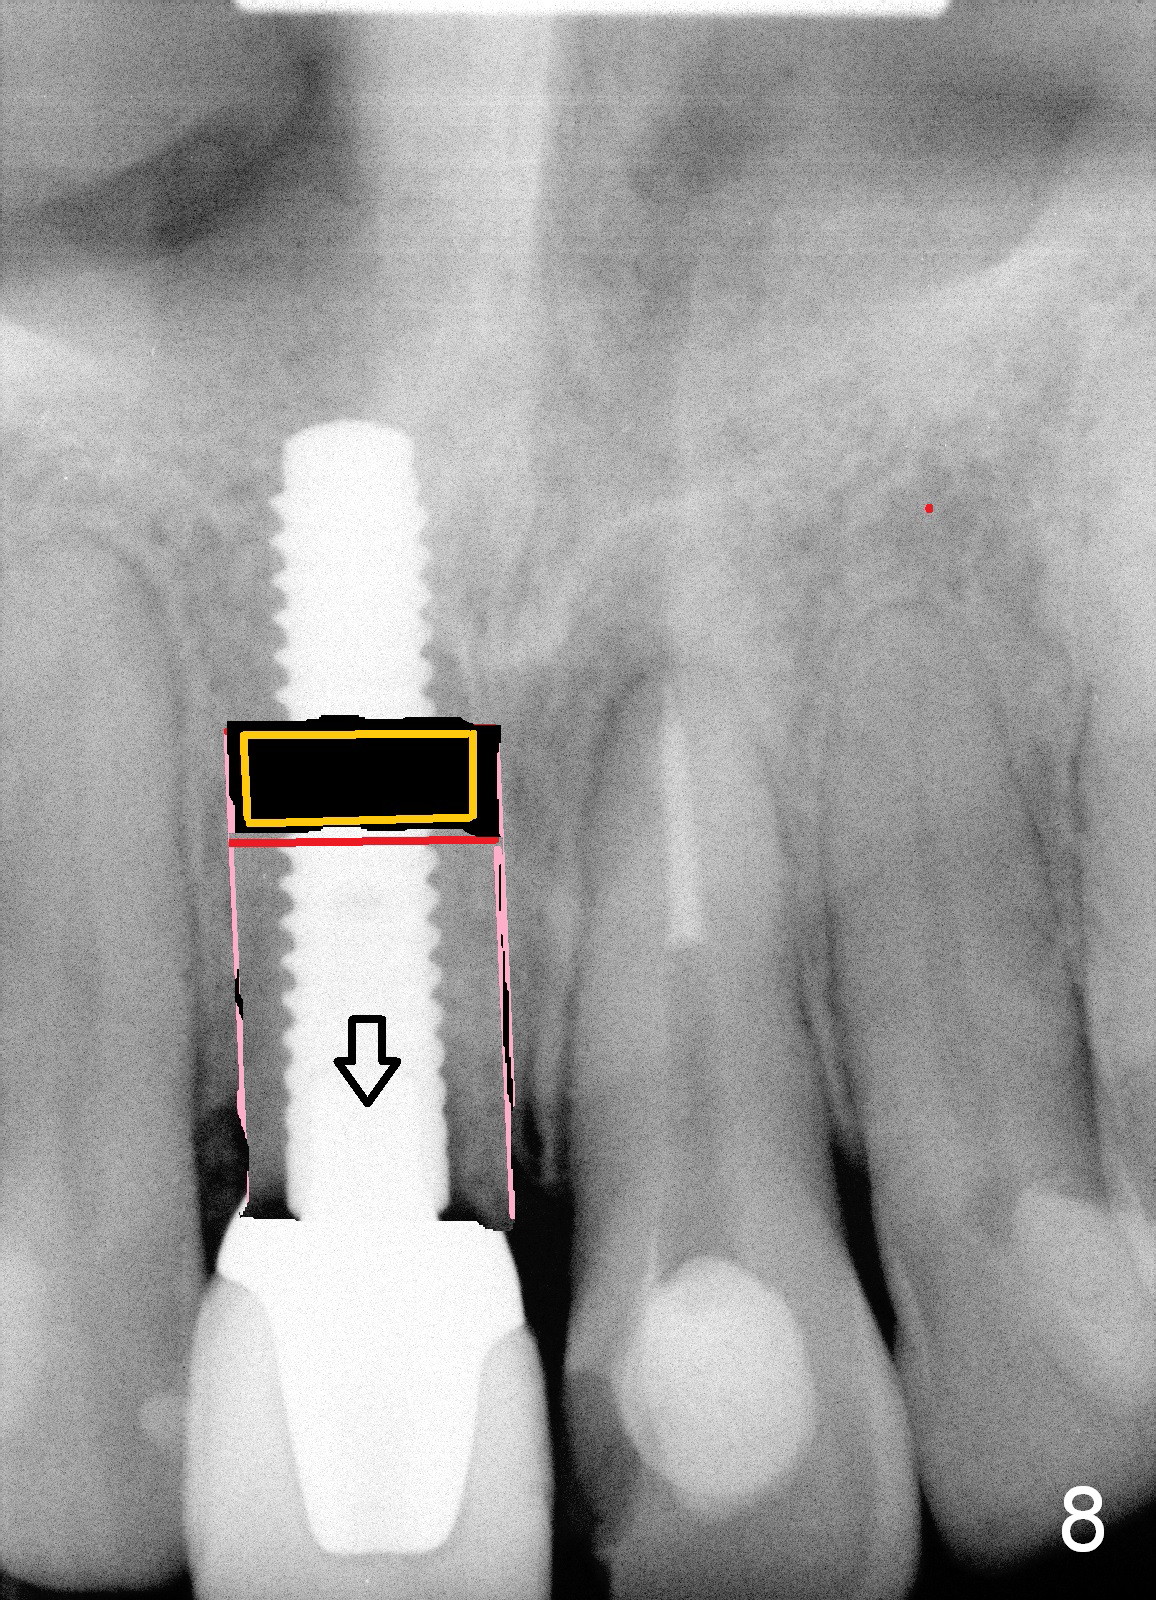

If segmental osteotomy is the only option, the transverse cut may be through the implant (Fig.7). There will be stable fixation (Fig.8).